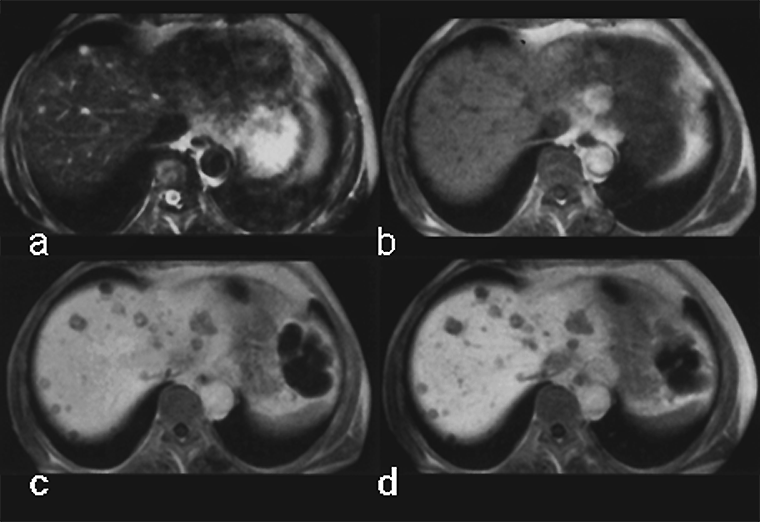

Although the chemical composition of Gd-BOPTA appears similar to that of the extracellular gadolinium agents, it combines both extracellular and liver-targeted properties, because some 5% of it is excreted through the liver, as is shown in this case of multiple metastases (Figure 13-14).

Figura 13-14:

Gadolinium-BOPTA in liver metastases of a pancreatic tumor.

(a) plain T1-weighted GRE sequence; (b) plain T2-weighted GRE sequence; (c) enhanced T1-weighted GRE sequence 40 minutes after injection; (d) T1-weighted GRE sequence 90 minutes after injection.